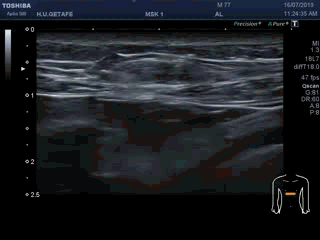

La imagen número 3 corresponde al corte en eje largo, mucho cuidado, siempre que tengamos el tendón del bíceps luxado, este se irá hacia medial, por eso, en eje largo vamos a encontrar la ecoestructura ligeramente hacia la axila, hacia medial.